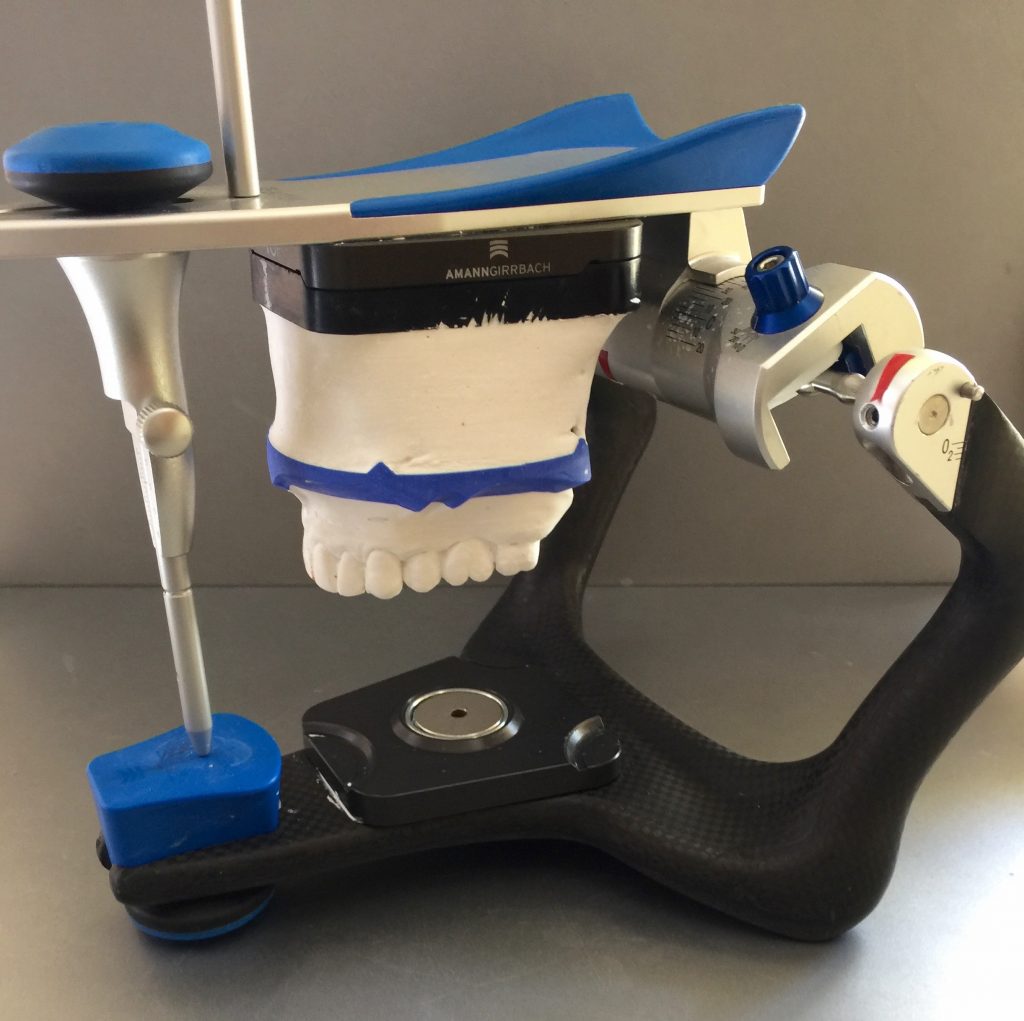

Autores: PRÓLOGO Asimismo, desde el punto de vista pedagógico, el profesional nobel en la materia tiene a su alcance la posibilidad de corregir cualquier posición implantaría en el ordenador, planear los provisionales y plasmarlos en la bio réplica antes de tocar al paciente a operar. Todos estos razonamientos nos llevan a presentar un caso de condiciones muy favorables para poner en práctica estos métodos como primer acercamiento a una Odontología Digital de alta calidad, con medios informáticos, que ya están presentes en la profesión de hoy en día, y será la protagonista única del futuro. Por otro lado, después de numerosos estudios que nos llevan a plantear el “gap” entre implante y pilar(abuttment), como principal responsable de la periimplantitis dado que la microbiota presente en el mismo es imposible de limpiar y en su presencia la cortical ósea reacciona reabsorbiéndose, nos ha llevado a utilizar implantes monobloc ya que los ejes implantarios y protéticos coincidían, y nos permitían su uso. Además, el circonio, ha mostrado a la luz de estudios muy recientes, una preservación y adhesión de los tejidos blandos superiores al titanio, tanto en su tratamiento de superficie de la rosca como a nivel gingival. DESARROLLO Paciente varón de 68 años, con antecedentes de radio/quimioterapia cinco años antes, con Rehabilitación Oral de los cuatro cuadrantes, con una Oclusión Mutuamente Compartida conservada, (REF.8) la que fracasa en el cuadrante 4, 19 años después. El mismo presentaba un puente de porcelana sobre circonio con pilares en 44 y 47, reemplazando el edentulismo de 45 y 46. Se produce la fractura del PM del 44, y ante una endodoncia antigua y corta, se decide implantar las zonas edéntulas, conservando temporariamente los pilares, hasta producida la oseointegración, para entonces también exodonciar el 44. DIAGNÓSTICO Tomamos impresiones del maxilar antagonista, Arco Facial Estático y realizamos montaje del mismo mediante la sistemática ARTEX. Producimos la relajación del músculo Pterigoideo Externo, para obtener la ORC (Oclusión en Relación Céntrica) mediante el método de Laminillas de Long, basado en el concepto de INERVACIÓN RECÍPROCA. Esto nos permitirá montar el maxilar inferior, tanto en su forma de: La primera para practicar la cirugía guiada y comprobar su eficacia, y el modelo de yeso para ser escaneado y confeccionar la GUÍA QUIRÚRGICA. La Biorréplica la obtenemos transformando los archivos DICOM que nos da el CBCT en archivos STL, y a partir de ellos, mediante una tecnología de PROTOTIPADO RÁPIDO, la obtención de un objeto físico en 3D a través de la aglutinación selectiva de una sucesión de capas de polvo. Procedemos a montar la biorrèplica y el modelo de yeso del caso. Podemos verificar la exactitud de las medidas del hueso residual en la bio réplica y compararlas con el scanner. Arrojando un resultado de 8,5 mm de cortical externa a cortical externa. Pudiendo también medir la distancia hasta el dentario. y comparar gracias a la ventana lateral de la biorréplica Dándonos 22mm de distancia. Con lo cual deducimos que implantes de 4,1mm por 12 mm serán perfectamente rodeados de hueso. Medimos también la distancia desde oclusal del antagonista, hasta el hueso desnudo. Lo mismo que, mediante la utilización de la guía radiológica, con un material radiolúcido colocado en gingival de la misma, podemos medir la altura de la encía. Con lo cual podemos calcular la altura del pilar. Es entonces cuando con el programa COC Diagnostix se realiza la programación final: Obteniendo no solo la ubicación, largo, ancho y ángulo de los implantes sino también los provisionales mediante CAD CAM. Ya entonces podemos hacer la práctica quirúrgica en la bio réplica, mediante la guía quirúrgica, instalando los implantes de prueba que no serán los de circonio, ya que la casa no cuenta con ellos, pero si otros de las mismas dimensiones. TRATAMIENTO Entramos ya en la cirugía propiamente dicha. Antisepsia de la zona a operar y zonas anexas. Comprobación del perfecto ajuste e inmovilidad de la G.Q. en boca durante la cirugía. Marcado de la encía y perforación de la cortical. Visión a través de la Guía de la mínima intervención anterior. Comprobación sin Guía. Incisión mínima mesio distal, para apartar y conservar encía queratinizada. Secuencia de drills, perforando a profundidad requerida Observación del Mínimo Trauma Implantes Strauman de Zirconio Monoblock en blíster y montádo en contrángulo reductor. Instalación controlando torque con contrángulo reductor. Comprobación clínica. Comprobación Radiográfica y con Guía. Toma de impresiones, y armado de modelos con técnicas de pasividad protética. Montaje. Resultado de las provisionales ejecutadas por CAD CAM Al no estar conformes con el resultado decidimos desechar dichas provisorias y optar por repetirlas. Nuevas provisorias realizadas mediante encerado convencional. Estado de los tejidos blandos. Provisorias en boca. Oclusión de Estímulo Inmediato. Ref.10: Carga inmediata .Alberto y Diego Bechelli. Comprobación mediante CBCT post operatorio Componentes del equipo (En la próxima presentación, mostraremos las coronas definitivas de porcelana sobre circonio, y la desoclusión provocada por una OCLUSIÓN MUTUAMENTE COMPARTIDA, sobre estos implantes y otros seis mas) REFERENCIAS

A-BIORRÉPLICA

Una vez obtenido el modelo matriz en polvo , se aplica un producto infiltrante para conferirle sus propiedades finales.

Los componentes del resultado final está compuesto por:

A-Sulfato de Calcio hemihidratado.(80-90%)

B-Solución acuosa con 2-Pirrolidona(0,1%)

C-2-Metoxietil-2-cianoacrilato(80-100 %)

REF.9

FIG: 14-15-16-17-18-19-20

FIG: 21-22-23-24-25-26

Fig. 21

Fig. 22

Fig. 23

Fig. 24

Fig. 25

Fig. 26